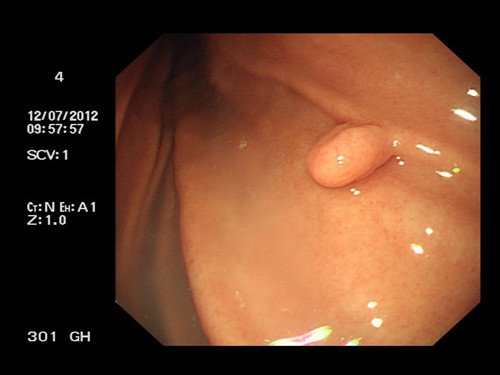

胃息肉癌變幾率有多大

胃息肉,是起源于胃黏膜上皮細(xì)胞凸入胃內(nèi)的隆起性病變。胃息肉較小時(shí)常無(wú)明顯癥狀,一般都是在胃腸鋇餐造影、胃鏡檢查或其他原因手術(shù)時(shí)偶然發(fā)現(xiàn)。我們知道,在胃癌的癌前病變中,就有胃息肉的一席地位。那么,胃息肉的癌變幾率到底有多大呢?

胃息肉是胃粘膜上皮或間質(zhì)成分增生所引起的息肉狀病變。胃息肉可分成非腫瘤性息肉(包括增生性息肉、錯(cuò)構(gòu)瘤性息肉、炎性息肉、異位性息肉等)和腫瘤性息肉(包括扁平腺瘤即管狀腺瘤和乳頭狀腺瘤即絨毛狀腺瘤)兩大類(lèi)。

胃息肉癌變的癌變率與有無(wú)不典型增生有很大的關(guān)系。腺瘤性息肉有不同程度的不典型增生,其有三種病理類(lèi)型:管狀腺瘤癌變率約10%、絨毛狀又稱乳頭狀腺瘤癌變率高達(dá)50%-70%、混合型腺瘤居于兩種之間。而增生性息肉屬于腺體增生延長(zhǎng),絕大多數(shù)無(wú)不典型增生,癌變率只有0.4%。

除了種類(lèi)的不同,胃息肉癌變的幾率還受息肉體積大小、患者病程、生長(zhǎng)速度等因素影響。其中息肉體積的大小就是很重要的一個(gè)因素。胃息肉的大小一般都不到一厘米,只有很少數(shù)的人增生性息肉會(huì)引起不良反應(yīng),癌變的幾率也較低;息肉直徑大于2cm、廣基、多發(fā)性息肉癌病率較高;當(dāng)胃息肉直徑大于3cm時(shí),癌變率更是高達(dá)70%。